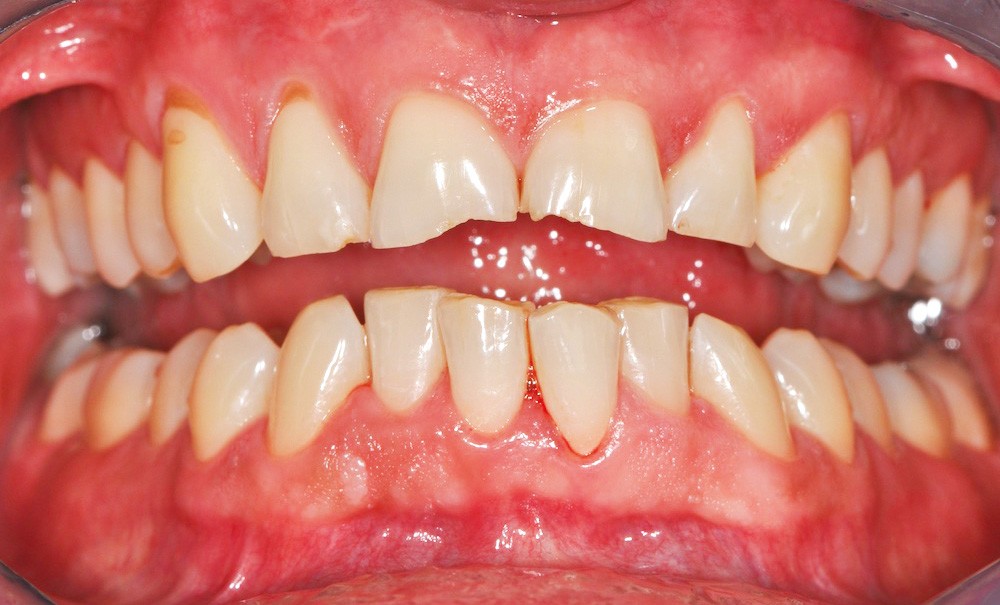

Dans les années 1980, deux praticiens américains, les Docteurs Franck Spear et John Kois, profitant des récentes avancées de la parodontologie, de l’orthodontie, de la chirurgie orale et maxillo-faciale, mais aussi en raison de la demande esthétique croissante des patients, ont proposé une nouvelle approche de la planification thérapeutique basée sur l’idée que si les dents sont correctement positionnées au sein de la bouche et du visage du patient, alors une fonction efficace en découlerait. A un plan de traitement ayant pour point de départ la position condylienne, ils ont préféré un plan de traitement ayant pour point de départ l’analyse dento-faciale et dento-gingivale.